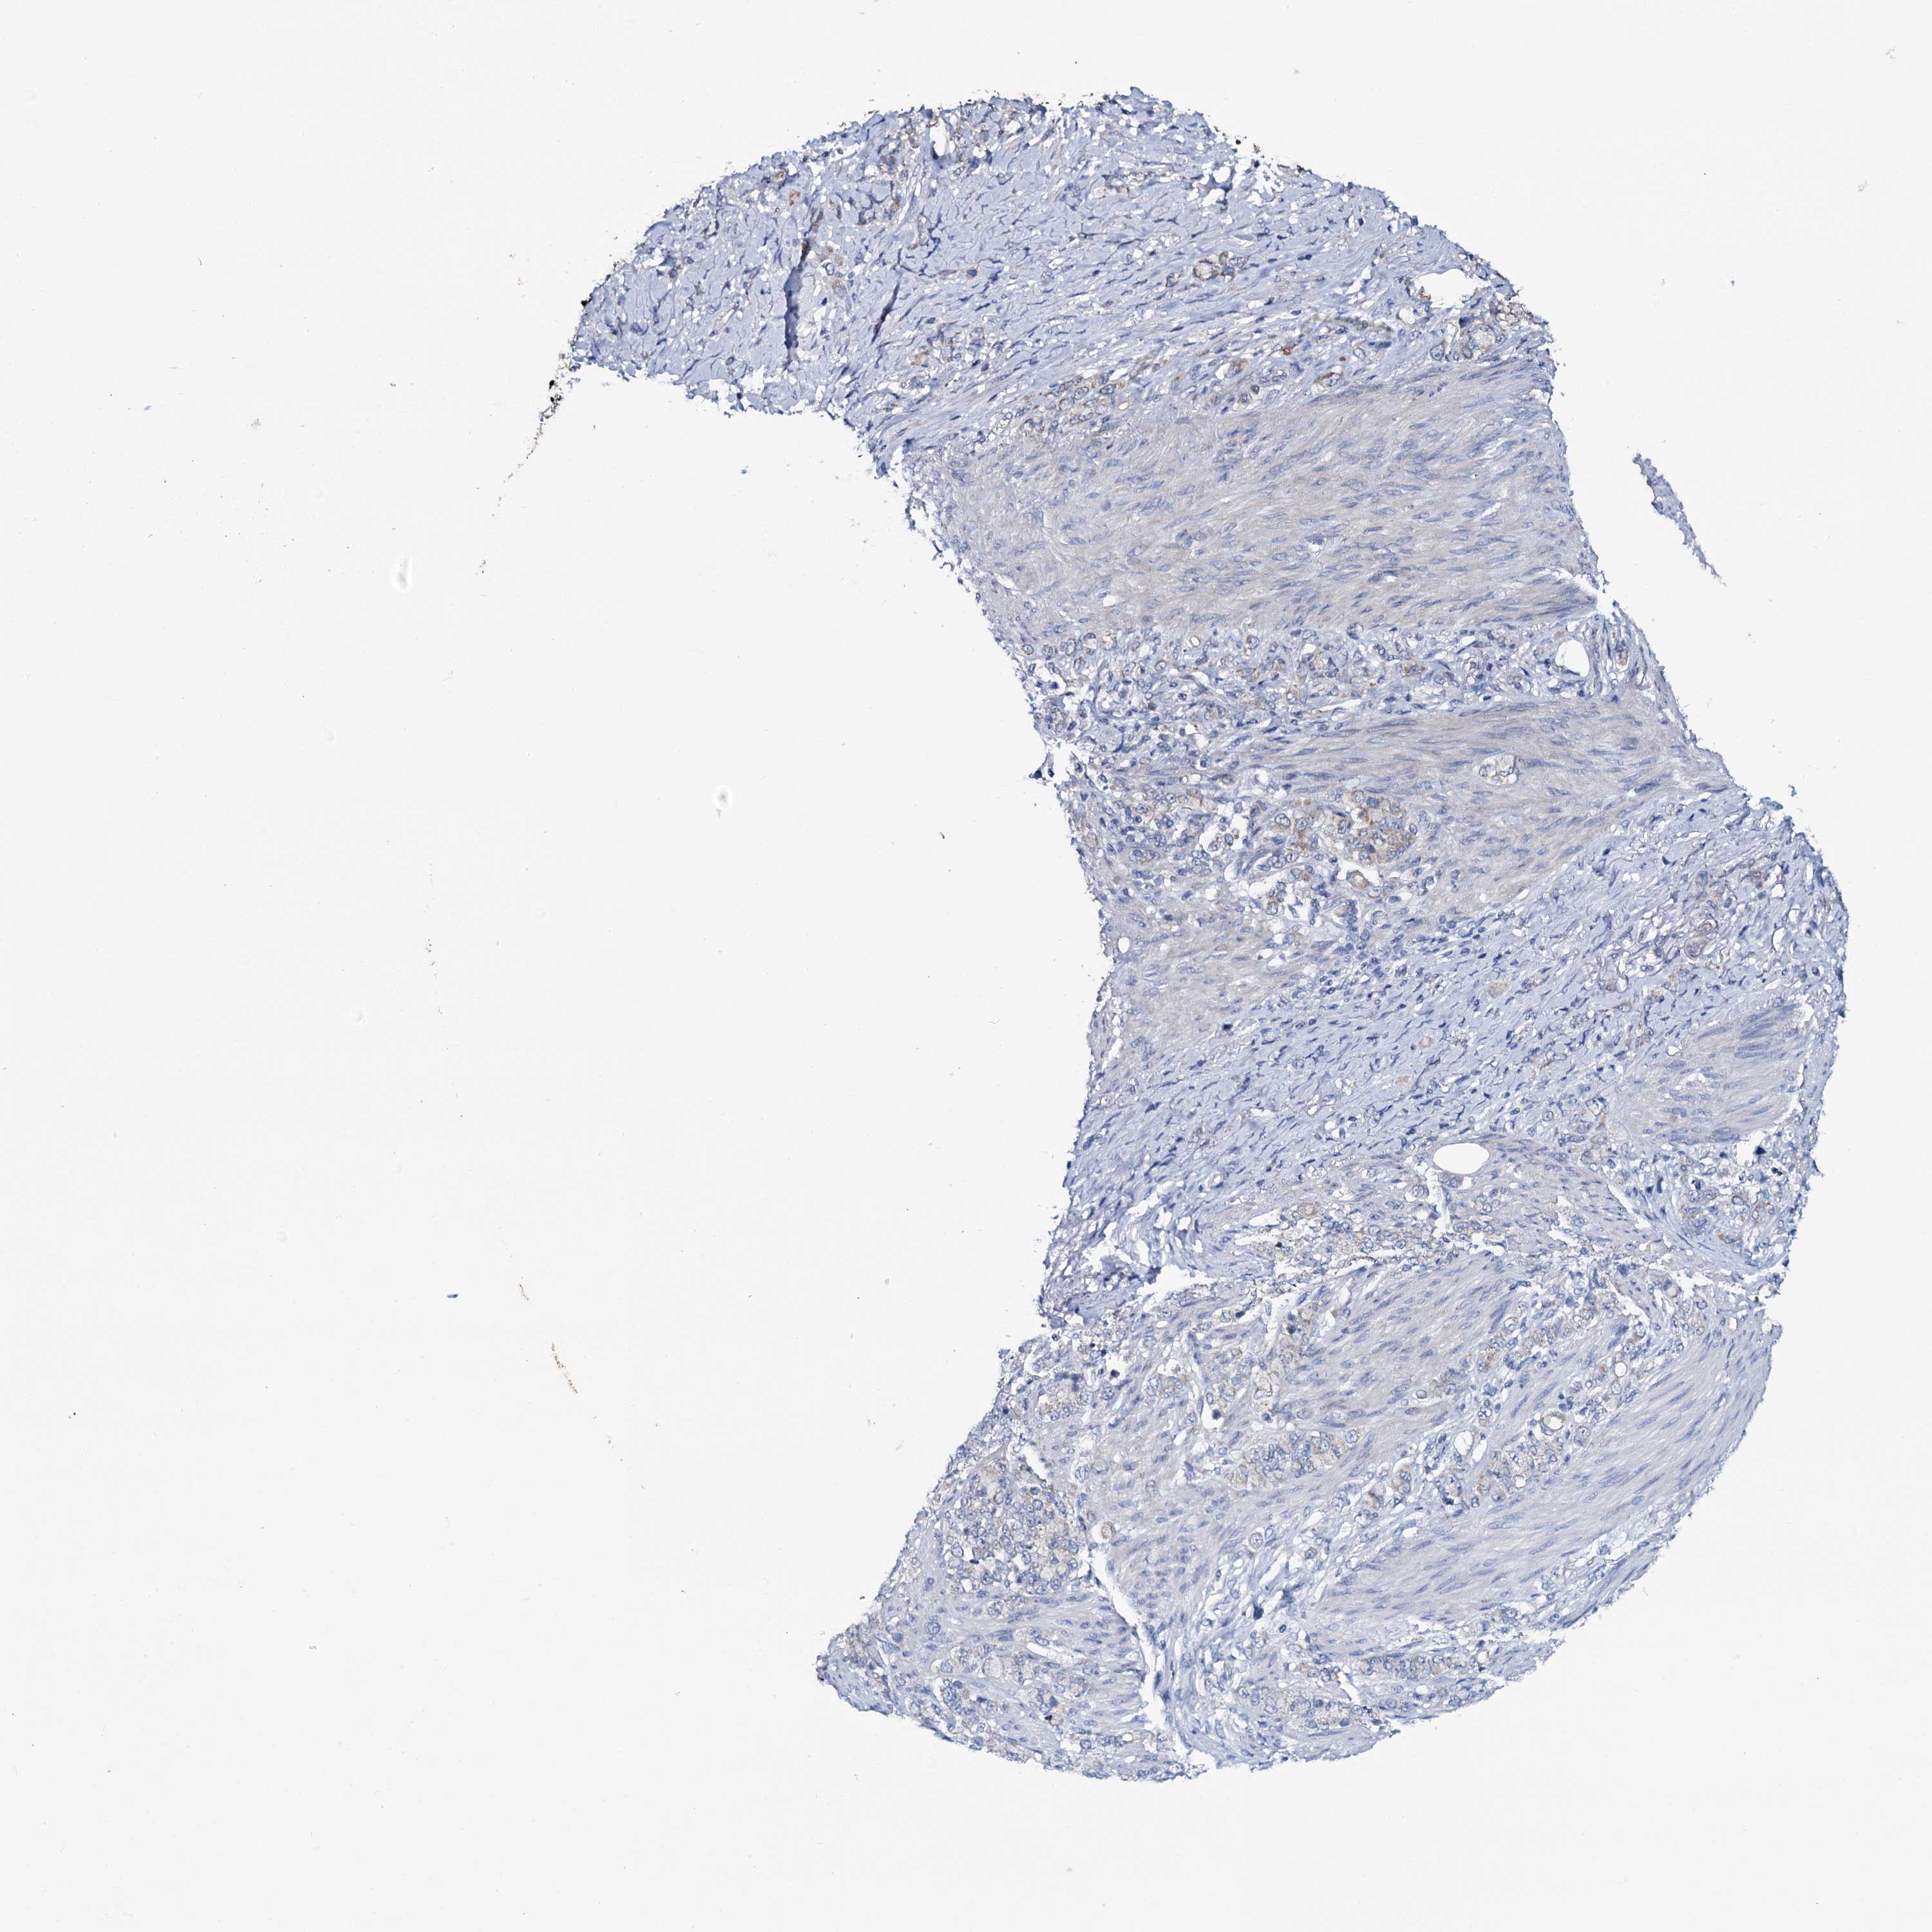

STOMACH CANCER - Protein expressioni

A mouse-over function shows sample information and annotation data. Click on an image to view it in a full screen mode. Samples can be filtered based on level of antibody staining by selecting one or several of the following categories: high, medium, low and not detected. The assay and annotation is described here.

Note that samples used for immunohistochemistry by the Human Protein Atlas do not correspond to samples in the TCGA dataset.

Antibody stainingi

Antibody staining in the annotated cell types in the current human tissue is reported as not detected, low, medium, or high, based on conventional immunohistochemistry profiling in selected tissues. This score is based on the combination of the staining intensity and fraction of stained cells.

Each image is clickable and will lead to virtual microscopy that enables deeper exploration of all samples and also displays staining intensity scores, fraction scores and subcellular localization as well as patient and tissue information for each sample.

Antibody HPA039083

Antibody HPA046344

Staining

High

Medium

Low

Not detected

Intensity

Strong

Moderate

Weak

Negative

Quantity

>75%

75%-25%

<25%

None

Location

Nuclear

Cytoplasmic/membranous

Cytoplasmic/membranous,nuclear

Adenocarcinoma, NOS

Adenocarcinoma, High grade